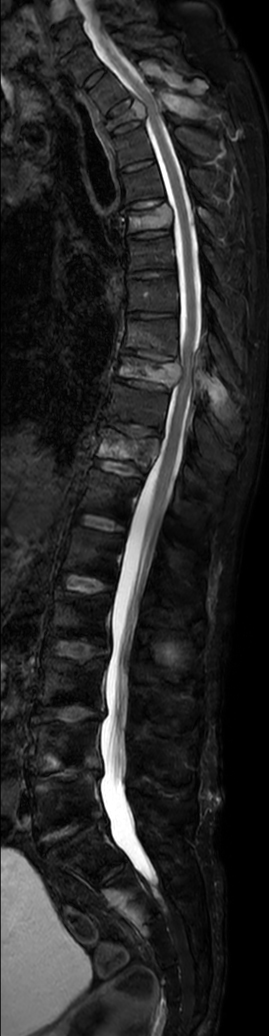

Patient with metastasis. Compressed SENSE is used to shorten the time on the table for the patient. The total spine T2w mDIXON sequence covers both the thoracic and lumbar spine in only 5:20 minutes, providing different contrast (Water only + In Phase). Compressed SENSE is also integrated in all other sequences to reduce scan time without losing image quality.

Sagittal T2w mDIXON XD TSE (Water only)